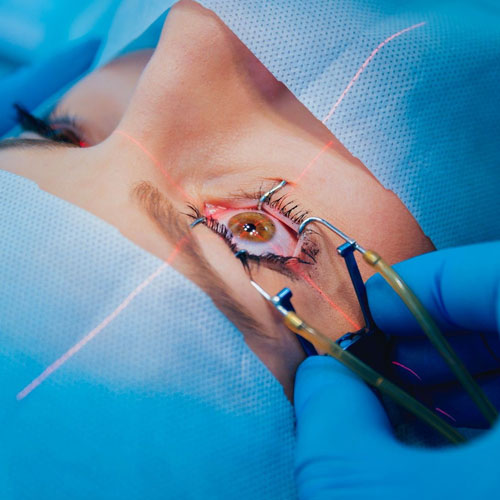

Dr. Abdul Rasheed, one of the leading Ophthalmologist and Cataract & Refractive surgeon in the city of Hyderabad provides extensive and comprehensive care for all your eye sight issues. Vision disturbance are one of the few issues which have the capacity to completely disturb our daily life and activities. Correcting them in the right way to avoid further complications or risk is the motto of Dr. Abdul Rasheed. With age comes cataract, Dr.Rasheed is an expert in complicated cataracts such as small pupil, zonular dialysis, mature / Brunescent cataracts, corneal scars, shallow Ac, etc., as well as complicated refractive surgery cases like RK scars, corneal scars, etc. While coming to refractive surgeries, Dr. Abdul Rasheed strongly believes and says "Any patient irrespective of complexity, who can be refracted to 6/6 can be treated to read the same without glasses." He has treated many patients of keratoconus who had extreme distortion of vision. After INTACS implantation followed by ICL, patients were able to regain normal vision.